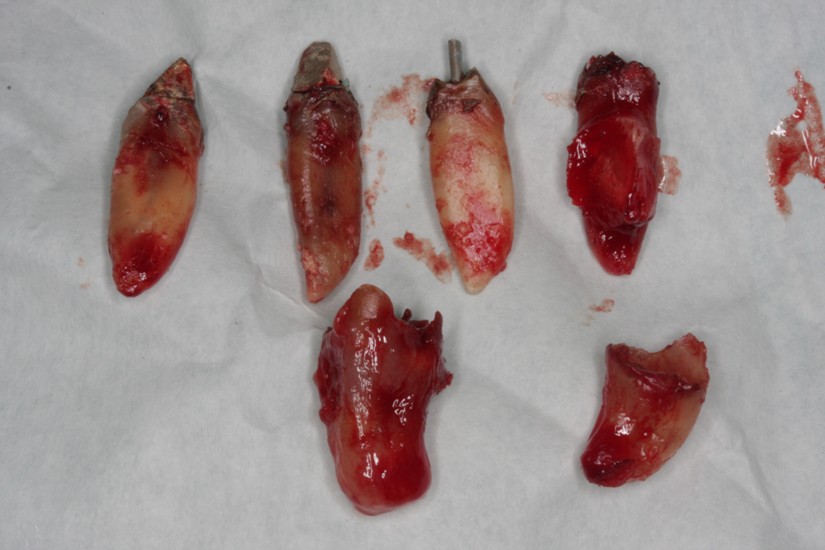

Removal of 15, 23, 31, 32, 38, 41, 42, 48 teeth and curettage of alveolar sockets were performed under infiltration anesthesia. The mucous membrane was cut along the alveolar crest in the area of 16, 14, 12, 22, 25, 36, 37, 46 and 47 teeth. Exfoliation of periosteal mucosal graft. Formation of bone bed. Placement of Alpha Dent Implants in the area of 12, 14, 16, 22, 25, 36, 37, 46 and 47 teeth (Photo 5). The implants are covered with screw-type plug. Suture of mucous membrane. Adjustment of temporary removable dental prosthesis. Administrations: antibiotic therapy, removal of stitches in seven days.